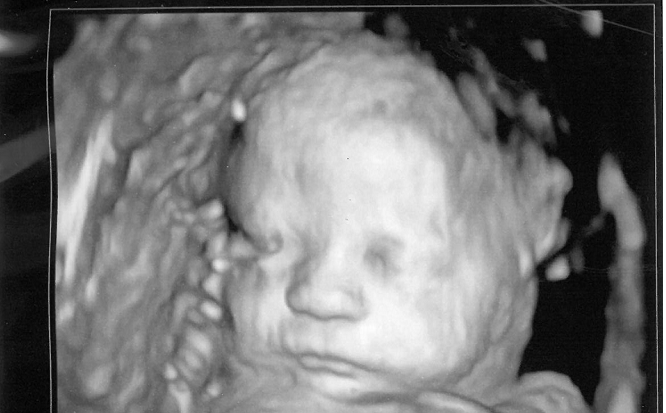

In addition, the sweeping Constitutional Amendment would end protections against brutal late-term abortions, upending our time-tested Pennsylvania law. The Amendment would mean abortion up to the moment of birth. Under current law, babies of six months’ gestation and older are protected from abortion, except in the rare cases where the life of the mother is at stake or the pregnancy would result in irreversible impairment of a major bodily function.